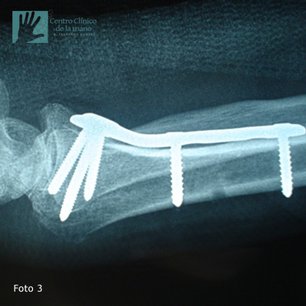

Fractura de Muñeca